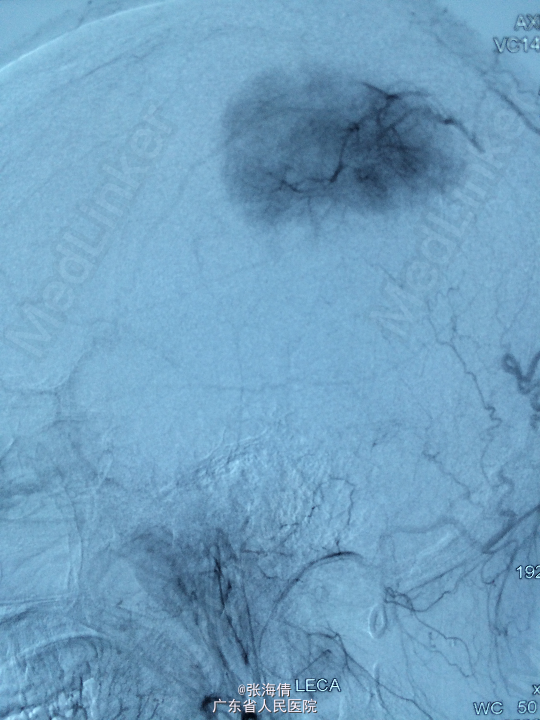

诊断:脑膜瘤 处理:先予DSA以明确肿瘤供血情况,术中脑膜瘤供血丰富,用PVA颗粒超选到供血动脉将其闭塞。后再择期在气管全麻下行脑膜瘤切除术。